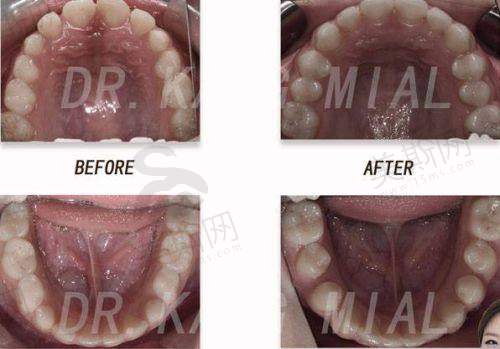

张栋梁医生通过“推磨牙向后 + 扩弓”联合方案,结合数字化牙弓分析,60%病例可避免拔牙。例如针对牙列拥挤患者,采用种植支抗推磨牙向后创造5 - 8mm间隙,配合上颌扩弓器拓宽牙弓宽度,实现牙齿排齐与咬合功能重建。儿童早期干预中,通过肌功能训练与骨龄评估,90%可避免恒牙期拔牙,该技术获北京市科技进步二等奖。

作为国内首批开展舌侧矫正的骨干医生,他研发的“个性化舌侧托槽系统”通过3D打印技术定制托槽角度,使矫治力作用点更接近牙阻抗中 心,在压前牙内收、上颌扩弓等方面成效提升40%。临床实例显示,骨性凸嘴患者采用舌侧矫正 + 颌位调整技术,18 - 24个月可实现侧貌从凸面型到直面型的转变,复发率低于2%。

针对重度骨性颌面畸形,张栋梁医生联合口腔颌面外科团队,创新“术前正畸 - 手术 - 术后精细调整”三阶疗法,通过数字化导板精细控制牙齿移动量,使正颌手术创伤减少30%,术后咬合精度误差≤0.5mm。典型实例包括32岁骨性开颌患者,经舌侧矫正 + 骨增量技术治疗,2年实现咬合功能修复,骨密度提升21%。